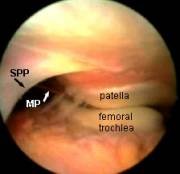

I've mentioned plicae already on this course. Although a plica is a normal structure, some people have them and some don't. They may differ in situation, size and thickness. If a medial plica is abnormal and thickened it can often be felt as a string-like object to the inner side (medial) of the patella. From the suprapatellar portal it is amazing how easy it is to see why medial plicae cause pain.

Look again at this region but this time from the front and side (all the left knee).

It should be clear that from the usual anterolateral portal one cannot see much of what is going on in this suprapatellar area because the bulge of the rounded femur gets in the way.

Certainly one cannot appreciate the plica being nipped between patella and femur in the way that you can from above.